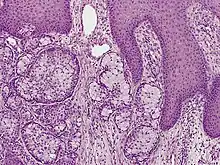

Eccrine carcinoma is a rare skin condition characterized by a plaque or nodule on the scalp, trunk, or extremities.[1]: 669 It originates from the eccrine sweat glands of the skin, accounting for less than 0.01% of diagnosed cutaneous malignancies.[2] Eccrine carcinoma tumors are locally aggressive, with a high rate of recurrence. Lack of reliable immunohistochemical markers and similarity to other common tumors has made identification of eccrine carcinoma difficult.[2]

A skin biopsy is the most common test used to diagnose eccrine carcinoma.[2] The biopsy will detect growth of new or abnormal tissue. Another test that can be performed is using immunohistochemistry, but it is inconsistent.[2] Markers used to detect eccrine carcinoma consist of carcinoembryonic antigen, progesterone receptors, estrogen receptors, epithelial membrane antigen, pancytokeratins, and cytokeratin 7.[5][6]